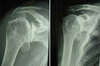

Les radios standards confirment la présence d’une arthrose centrée (sans rupture de la coiffe).

Il faut demander un arthroscanner qui confirmera l’importance de l’usure cartilagineuse et osseuse, et la bonne continuité de la coiffe.

Arthroscanner d’épaule